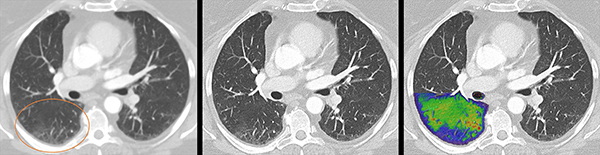

心臓や肺といった領域も高速撮影により明瞭な画像を得られるほか,スペクトル情報を利用してヨードマップや最適なコントラストのmonoenergetic imageなどを作成できる。心臓では,石灰化を除去したPURE Lumen(純粋な内腔)を観察でき,石灰化の強い患者やステント留置後のフォローアップでも診断価値の高い画像を取得可能だ。また,COVID-19症例では,一度の低線量撮影で高分解能画像による肺炎の評価,スペクトラルイメージでの血流の評価が可能になることなどが紹介された。

COVID-19症例(左:従来CT,中:NAEOTOM Alphaの高分解能画像,右:スペクトラルイメージによる血流評価)